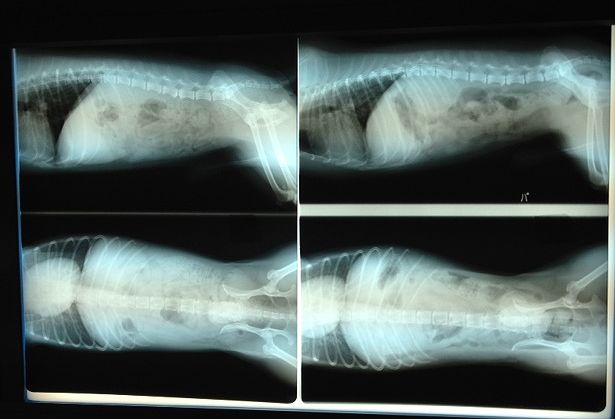

腹部のレントゲン写真です。

レントゲンで肝臓が大きく写っているんですがエコー検査でも異常がなかったらしく、どうも写真の撮った角度で大きく写ってしまった様ですとの事でした。

パピは心臓の件があるのでエコー検査もしてもらいましたが、こちらも特に問題はなかった様です(写真は撮り忘れました)

パピが僧帽弁閉鎖不全症と診断され約1年、悪化はしてないようなので安心しました。